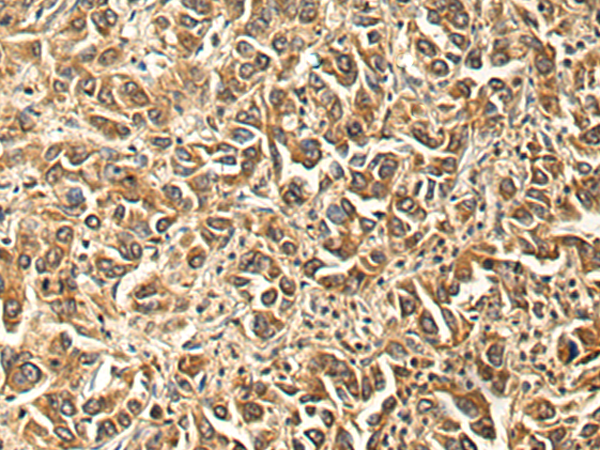

IHC positive control: |

Human liver cancer |